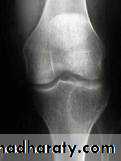

show a radiolucent area situated eccentrically at the end of a long bone and bounded by the sub- chondral bone plate.

The endosteal margin may be quite obvious, but in aggressive lesions it is ill-defined.

X-rays42

The Centre sometimes has a soap-bubble appearance.

The cortex is thin and sometimes ballooned. aggressive lesions extend into the soft tissue.43

The appearance of a ‘cystic’ lesion in mature bone, extending right up to the subchondral plate, is so characteristic